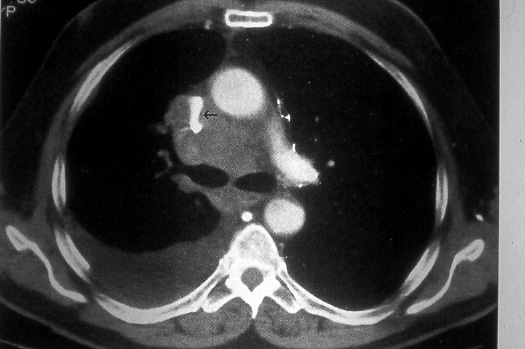

Stage IIIB

Fig. 48b: Computed tomographic scan of the chest shows marked compression of the superior vena cava (black arrow) from right upper lobe bronchogenic carcinoma; extensive mediastinal adenopathy is present and a right pleural effusion is seen, T4 N2 M0, stage IIIB.